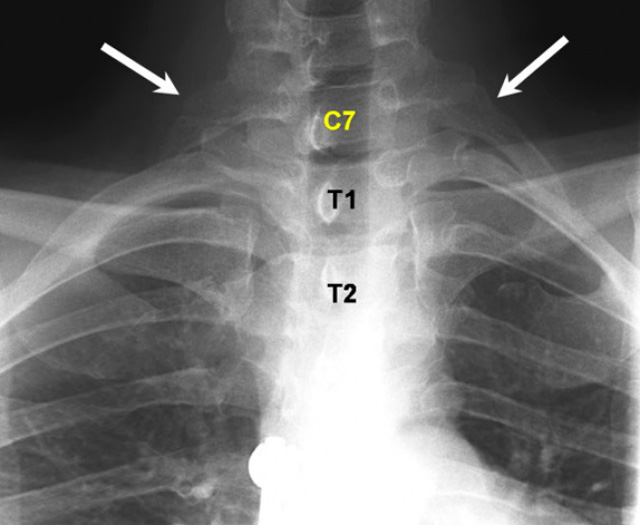

7. Có thêm xương sườn

Chứng bệnh này thường gặp ở phụ nữ. Những chiếc xương sườn mọc thêm này thường phát triển ở gần cổ tử cung. Trong hầu hết các trường hợp, việc mọc thêm xương sườn không ảnh hưởng đến sức khỏe trừ khi chúng phát triển quá lớn và gây khó chịu.